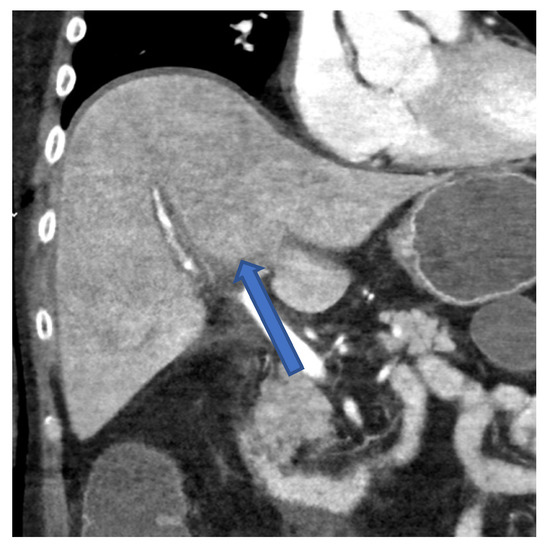

Figure 3.

CT scan of the abdomen in frontal plane of case 1 showing an irregular contrasted liver parenchyma 2 days before the patient died.

Transjugular biopsy of the liver revealed multifocal hepatocellular necrosis and a lobular chronic inflammation consistent with a viral hepatitis (Figure 2a). Histopathologically, a GvHD, as well as cytomegalovirus (CMV) and EBV infection, could be excluded. A CT scan presented an irregular contrasted parenchyma, a hepatic edema, and a dilatated common bile duct (Figure 3). Treatment with 325 mg of cidofovir and immunoglobulins was applied immediately after HAdV was diagnosed. The coagulation dysfunction was aggravated with recurrent bleeding complications. In addition, a central pulmonary embolism deteriorated the respiratory situation with development of treatment-resistant lactic acidosis caused by ALF. The patient died only 4 days after symptom onset due to fulminant multiorgan failure in disseminated HAdV infection.

A PCR of the blood is considered the gold standard for diagnosing a HAdV viremia [5]. In addition to PCR, diagnosis of hepatitis with subsequent ALF can be confirmed by CT scan (Figure 3) and by liver biopsy (Figure 2), as shown in cases 2 and 3.